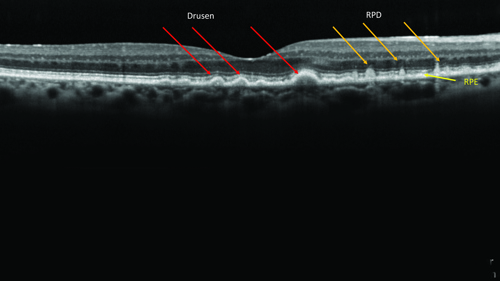

The early stages of AMD are diagnosed by the presence of drusen. The size and extent of the drusen present in the macula determine the risk of disease progression. Patients with larger drusen (>125μm) are considered to have intermediate AMD and be at a greater risk of progression compared to those with smaller drusen. With the advent of spectral-domain optical coherence topography (OCT) imaging techniques it is now possible to distinguish more accurately different deposits at the macula. Imaging with OCT distinctly locates RPD above the retinal pigment epithelium (RPE). RPD have a distinct appearance on SD-OCT and their location above the RPE clearly distinguishes them from conventional drusen which are below the RPE (Fig 1). RPD are often difficult to see on colour fundus photographs and clinical examination and as such are often missed. Development of infra-red reflectance scans and fundus autofluorescence (FAF) technology has helped to distinguish these lesions but OCT-B scans are the best way to visualise these deposits. RPD appears to place people at greater risk of AMD progression, but little is known about what causes RPD deposits or how they affect AMD progression, though they are considered important in disease pathogenesis as they are frequently present in late-stage AMD.

Fig 1. RPD occur on top of the RPE, so are called subretinal drusenoid deposits (SDD)